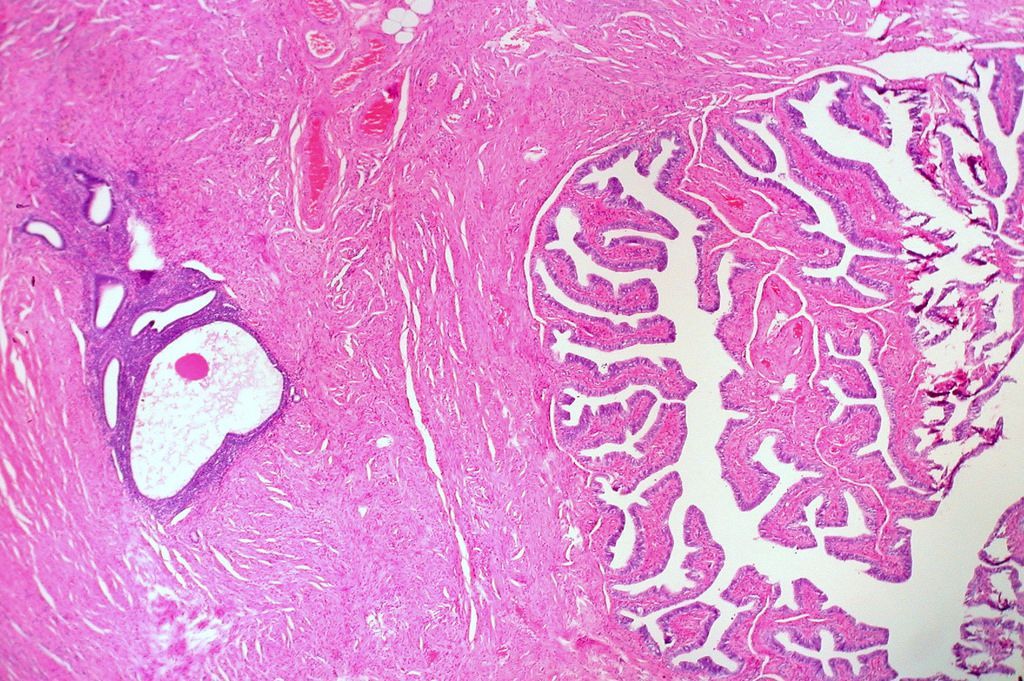

La endometriosis es un trastorno crónico en el que las células del revestimiento de la matriz crecen fuera del útero. Esta condición, que ocurre en aproximadamente un 10% de las mujeres en edad reproductiva, puede ser dolorosa, especialmente durante la menstruación e incluso puede causar infertilidad. Actualmente existen diferentes tratamientos hormonales e incluso quirúrgicos que pueden ayudar a tratar la endometriosis, pero algunos de ellos tienen efectos secundarios no deseados.